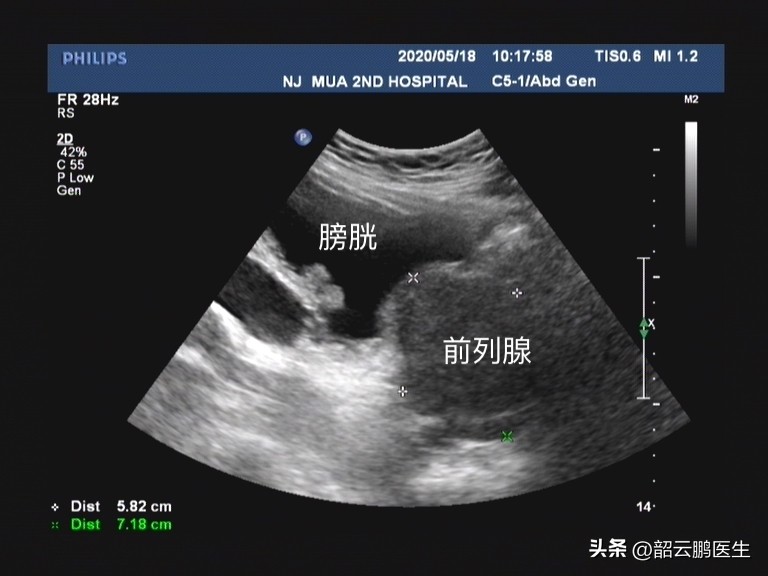

中医对于前列腺增生的诊断归属于 “精癃”、“癃闭”、“淋证” 等范畴,认为前列腺增生的基本病机主要是 三焦失司,膀胱气化不利,病变部位在精室 。根据病因又有虚实之分,实证多以精室湿热、精室瘀阻、肺气郁闭、肝郁气滞等 为主;虚证有中气下陷、肾阴亏虚、脾肾气虚等,尤其与肾密切相关。

细数常见证型主要分为9种类型,包括 精室湿热、精室瘀阻、肺气郁闭、肝郁气滞、中气不足、肾气不固、肾阴亏损、脾肾气虚、肾虚血瘀 。临床上多为两个或两个以上证型同时出现,而在针对病因病机进行治疗时, 需要基于“脑-心-肾-精室”轴 ,从整体的观念来对前列腺增生的治疗进行分析。